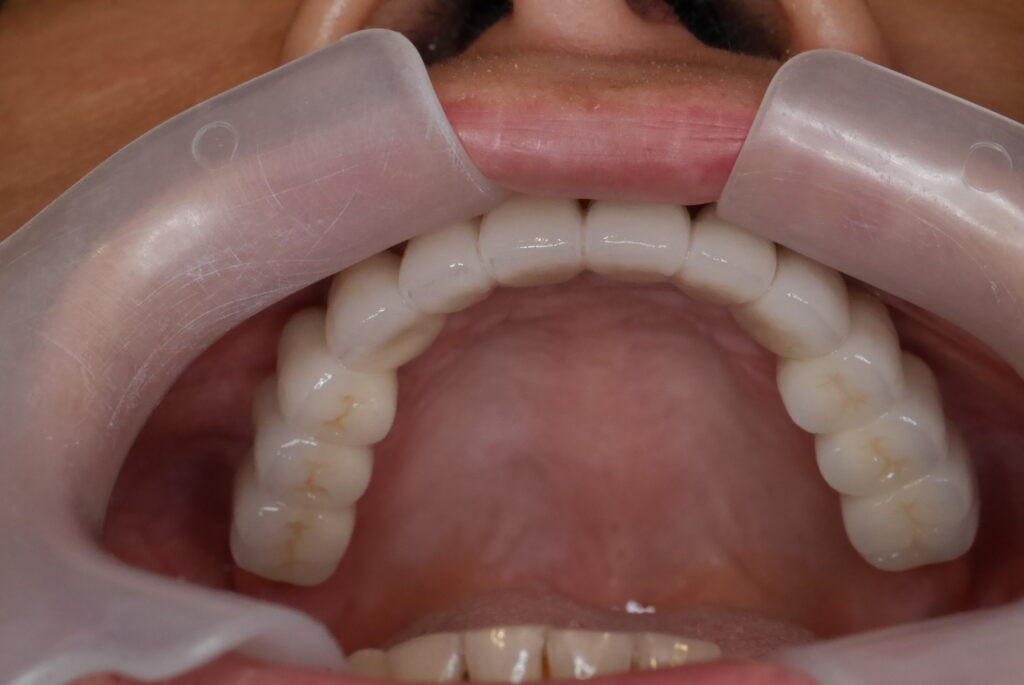

假牙完成